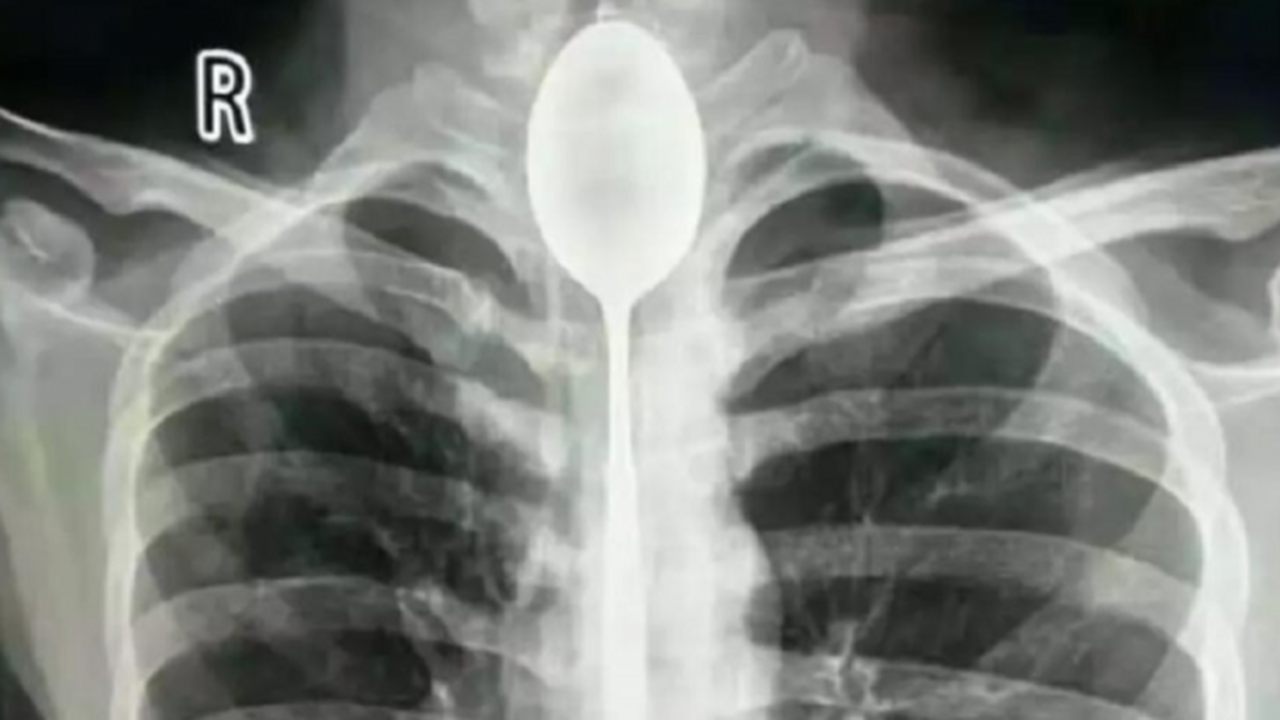

İsminin Zhang olduğu öğrenilen şahıs, ‘yapabildiğini göstermek için’ 20 santimlik bir kaşığı yuttu ve uzun süre bu şekilde yaşadı. 20’li yaşlarında olan Zhang, göğsünden yumruk yiyene kadar boğazındaki kaşıkla ilgili herhangi bir problem yaşamadığını belirtti.

Çin’in ünlü sosyal medya platformlarından weixin’de yer alan açıklamada, nefes almakta güçlük çektiğini belirterek hastaneye giden Zhang’la ilgili yapılan incelemeler sonucunda, şahsın boğazındaki kaşık tespit edildi ve acilen ameliyata alındı.

İki saatten fazla süren operasyonun ardından Zhang’ın boğazındaki kaşık çıkarıldı.

Zhang’ın ameliyatını gerçekleştiren doktorlardan Yu Xiwu, yaptığı açıklamada, “Çok şaşırdım, daha önce böyle bir olayla karşılaşmamıştım” ifadelerini kullandı. Hastane tarafından yapılan açıklamada, Zhang ‘şanslı’ olarak nitelendirildi ve metal objeleri yutmanın hayati risk taşıyabileceği vurgulandı.

Doktorlar ayrıca kaşığın ciddi bir enfeksiyona neden olabileceğini söyledi.